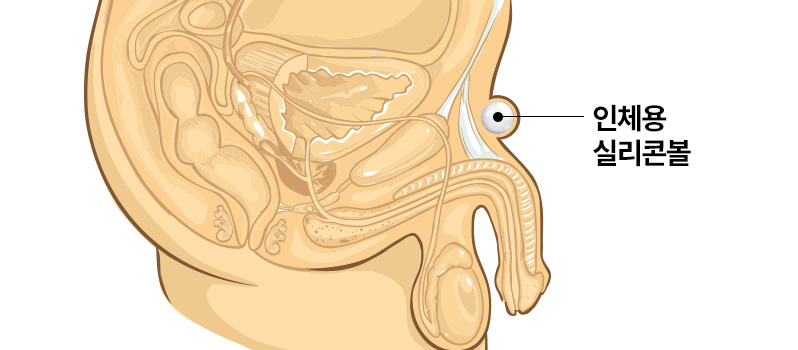

UROGYN 치골융기수술

수 술 방 법

수술과정!

음경뿌리 바로 윗부분에 약 2cm 가량의

절개를 진행 후 KFDA 승인을 받은

인체용 실리콘볼을 삽입 후 마무리합니다- 수술시간

30분 내외 - 마취방법

국소마취 - 실밥제거

약 2주 후